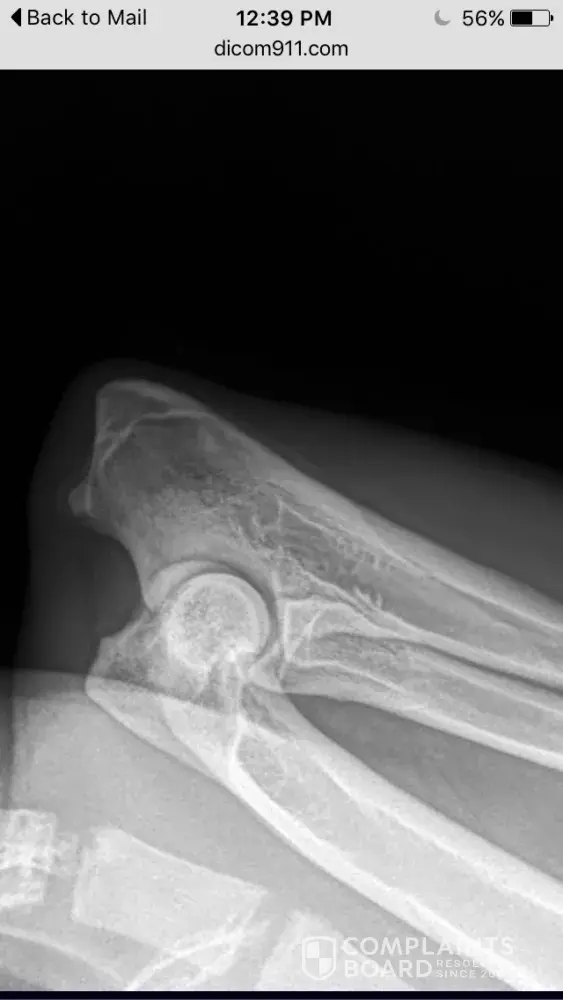

In December 2014, I purchased a german shepherd puppy from Tropisch German Shepherds. When my puppy was 8 months, he started limping and it continued for a few days so I brought him to my vet. The vet gave him anti-inflammatory pills and the limping went away after a few days. The limping came back about a month later and again, I went to my vet and she gave him anti-inflammatory pills and the limping went away after a few days. My vet told me that if the limping came back a third time, we would have to do an x-ray. The limping came back and about 2 months ago, my dog had the x-ray which revealed the beginning stages of hip dysplasia, panosteitis and arthritis. My vet told me these conditions are progressive and there is nothing I can do to prevent it. I am devastated and disgusted with this breeder. She is young, inexperienced and obviously doesn't care that she is breeding dogs with health problems and selling the puppies to people just for the money. I love my puppy and I am going to give him the best life I can possibly give him, but people need to know that Tropisch German Shepherds is dirty and they breed dogs with health problems. Please stay away from this breeder.